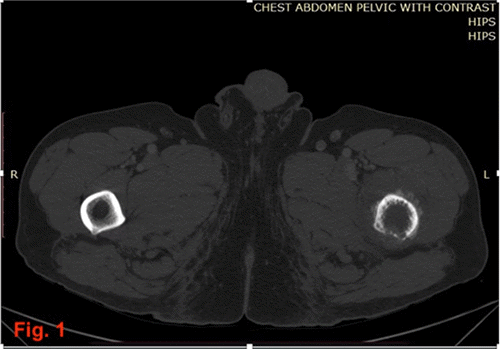

While an urgent oncologic colorectal resection was planned, definitive orthopedic intervention for the stable pathological fracture was initially postponed. This decision was influenced by the patient’s preference to be treated by a specific orthopedic surgeon unavailable at our institution and the near-obstructing nature of the colonic tumor, which prioritized the colorectal surgery. The patient underwent an oncologic laparoscopic low anterior resection under general anesthesia, performed by a board-certified colorectal surgeon assisted by a PGY-5 resident. The perioperative, intraoperative, and immediate postoperative course was unremarkable. Due to his underlying congestive heart failure, he was transferred to the intensive care unit for close cardiac monitoring postoperatively and was subsequently moved to the surgical ward on postoperative day (POD) 3. On POD 4, while ambulating in his room, the patient reported hearing a “cracking sound” and experienced a fall. A spontaneous, closed, displaced left femoral shaft fracture with associated skin tenting was diagnosed. Orthopedic surgery was consulted immediately; the fracture was reduced, and a Buck’s traction device was applied (Figure 2). This unexpected event prompted further surgical intervention, consisting of intramedullary nailing of the femur, during which a bone biopsy was obtained. Histopathological examination of this biopsy unequivocally confirmed metastatic colorectal adenocarcinoma as the underlying cause of the pathological fracture.

Figure 2. Post-Reduction Radiographs of Left Femur with Buck’s Traction. Published with Permission

(A) Anteroposterior and (B) Lateral radiographs of the left femur obtained after closed reduction of a spontaneous pathological shaft fracture. The images demonstrate alignment of the fracture fragments with a Buck's traction device in place